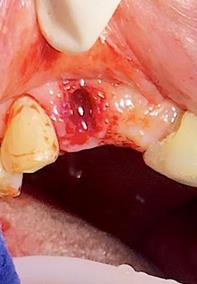

Sindesmotomía con un periostótomo de molt # 9, posteriormente se realizó la luxación con un elevador recto, buscando el punto de apoyo, seguido se efectuó la prensión con el fórceps 150 en el diente con sumo cuidado de no tocar la encía colocándolo hasta el cuello dental, haciendo movimientos de lateralidad y rotación hasta lograr la dilatación del alveolo, y finalmente la tracción del órgano dentario, observando que la raíz este integra, y que estructuras alrededor estén conservadas, de la misma forma se revisó el alveolo en busca de la presencia de granulomas o espículas óseas, una vez ya revisado se procedió al curetaje, con una cucharilla de lucas, se introdujo y se dio paso al retiro del exudado purulento, se realizó irrigación del alveolo con solución fisiológica, una vez limpio se realizó una sutura simple con sutura nylon, seda # 3/0 en el medio del alveolo con la finalidad de aproximar rebordes, evitar su contaminación por el ingreso de comida, además generar una mejor cicatrización en una zona estética , finalmente se aplicó presión por medio de una gasa que mordió el paciente por un lapso de 30 minutos, para contribuir con una hemostasia adecuada.

Figura 7. Exodoncia de la unidad dental, revisión del alveolo, curetaje y retiro de exudado purulento con cucharilla de lucas.

Elaboración: Los autores.